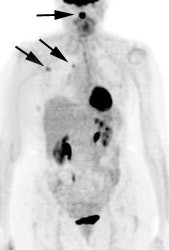

FDG PET exam results in breast cancer patient guide therapy: The patient shown below was a 40 year old female who had undergone lumpectomy and adjuvant chemo/radiation therapy for breast cancer. Ten months later the patient began to experience pain in the right shoulder. A bone scan and CT scan were interpreted as negative. The FDG PET exam revealed numerous foci of tracer accumulation within the right axilla and chest consistent with metastatic disease. As a result of the PET exam findings the patient was treated with another course of chemo/radiation therapy. The exam was performed on a Siemens ECAT EXACT PET scanner; 10 mCi FDG, and 5 bed positions. Case courtesy of Rush-Presbyterian-St. Luke's Medical Center, Chicago, IL and CTI. |

|